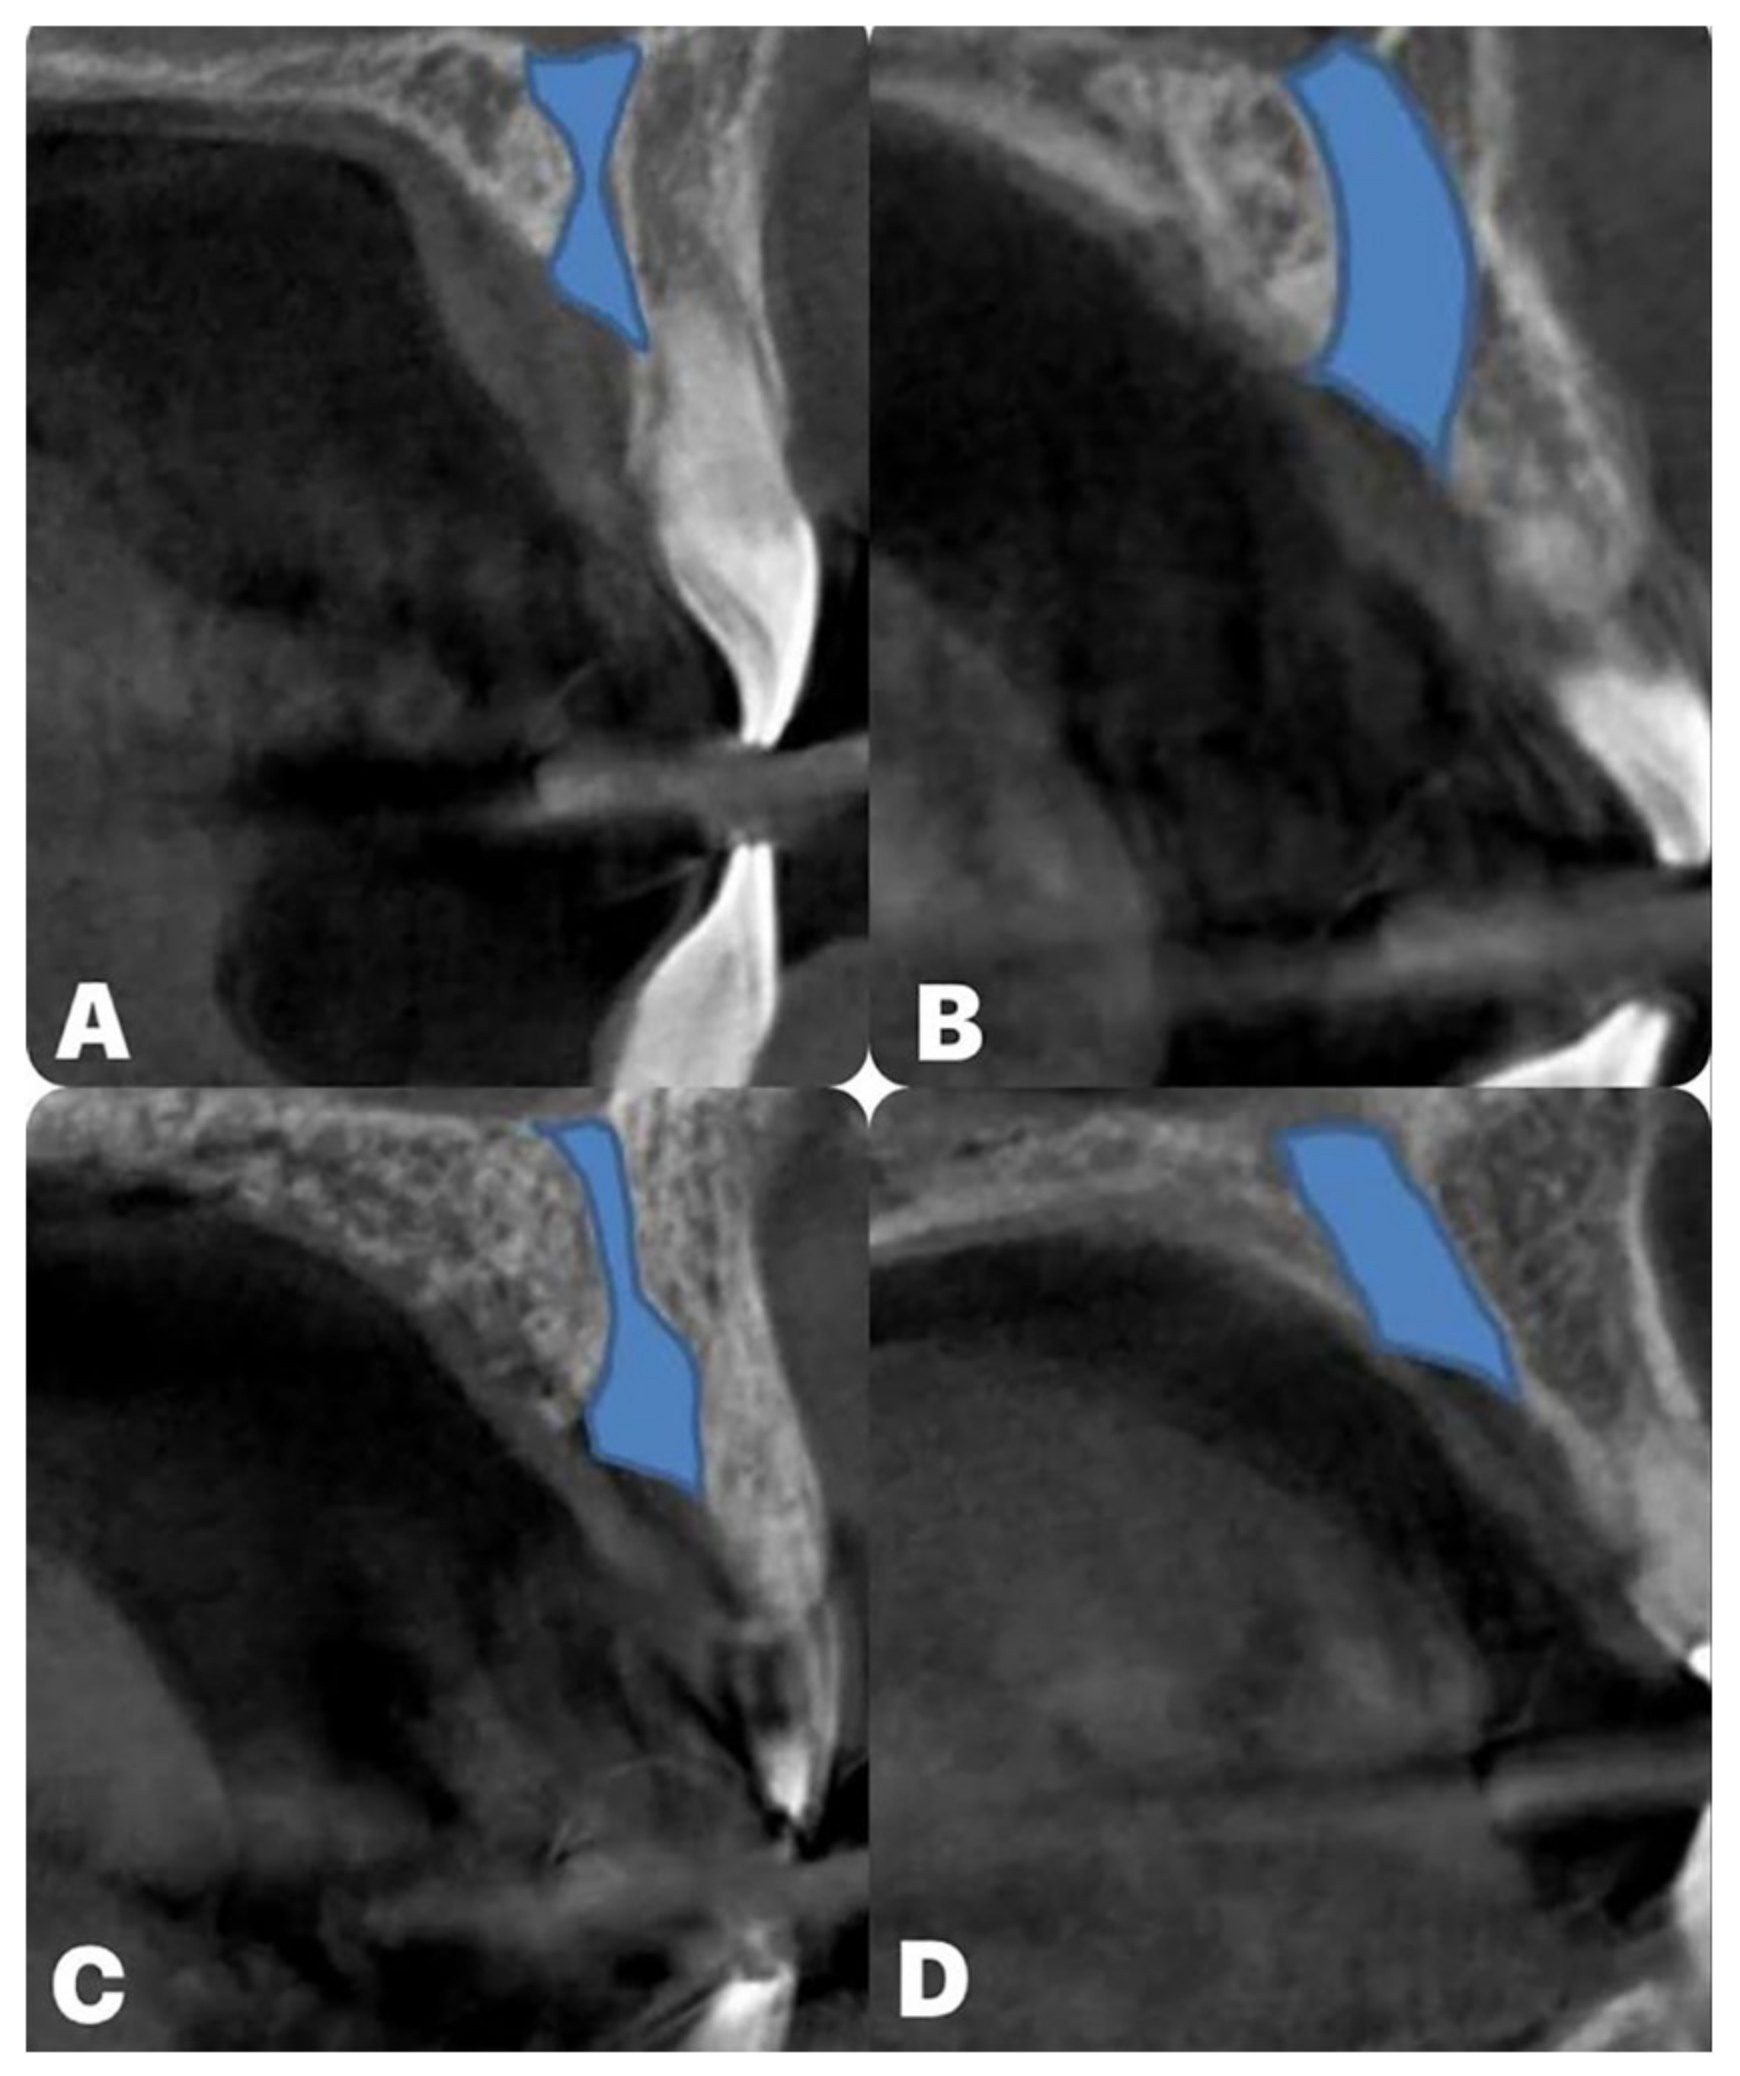

- Arnaut, A.; Milanovic, P.; Vasiljevic, M.; Jovicic, N.; Vojinovic, R.; Selakovic, D.; Rosic, G. The Shape of Nasopalatine Canal as a Determining Factor in Therapeutic Approach for Orthodontic Teeth Movement—A CBCT Study. Diagnostics 2021, 11, 2345. [Google Scholar] [CrossRef] [PubMed]

- Milanovic, P.; Selakovic, D.; Vasiljevic, M.; Jovicic, N.U.; Milovanović, D.; Vasovic, M.; Rosic, G. Morphological Characteristics of the Nasopalatine Canal and the Relationship with the Anterior Maxillary Bone—A Cone Beam Computed Tomography Study. Diagnostics 2021, 11, 915. [Google Scholar] [CrossRef] [PubMed]